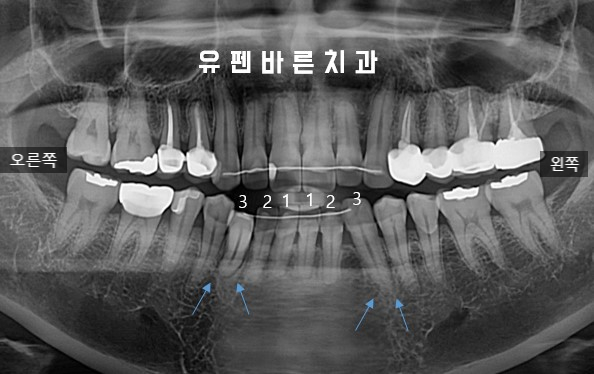

Comparing the Roots of L3s

엑스레이에 보시는 것처럼

반대편 송곳니와 비교했을때도

치아가 뻐드러져 뿌리가 짧게 보이고

교정적으로 틀어진 각도를 잡아주지 않으면

치아의 수명에 치명적인 상황이었습니다.